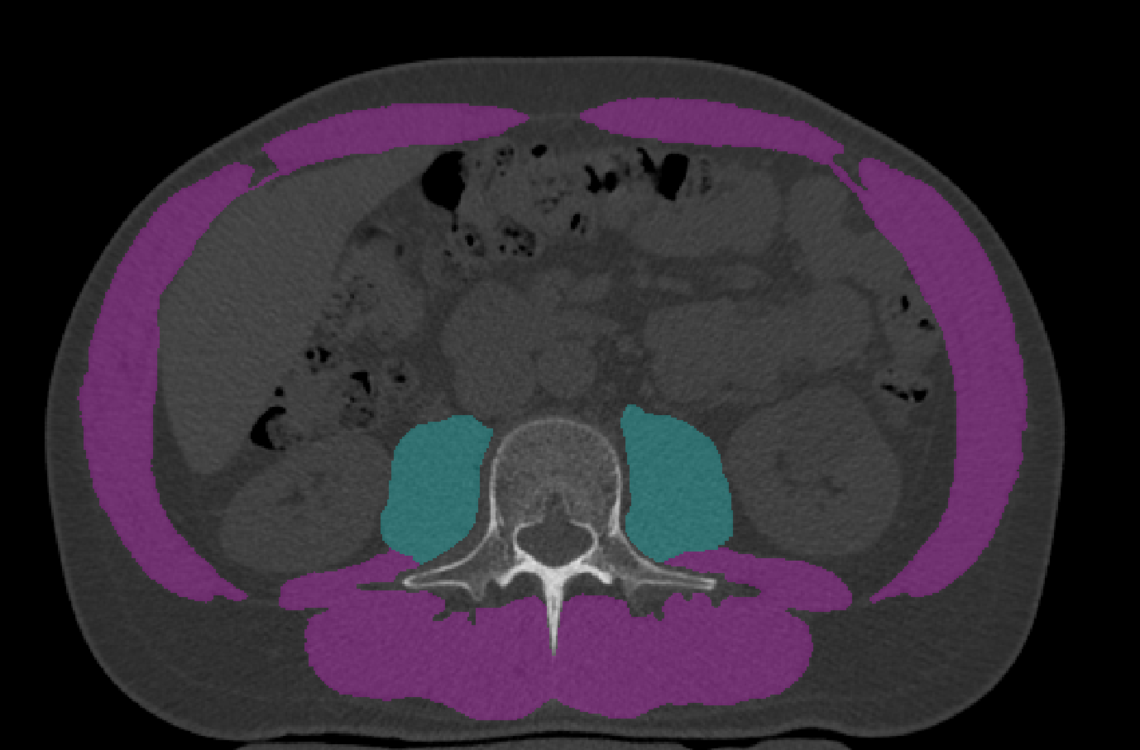

Muscle loss can lead to weakness, fracture, and a reduced quality of life. In critical care patients, low muscle density is linked to higher mortality, and in survivors, symptoms of this muscle loss as well as bone loss can persist long-term. CT images taken of patients at admission and discharge can be analyzed retrospectively using a recently developed internal calibration method to evaluate muscle and bone health outcomes. Understanding the complexities of care and specific challenges that individuals experience could help indicate risk factors for bone and muscle loss, as well as better inform treatment options. This project aims to utilize these opportunistic clinical CT scans to validate the internal calibration method for muscle density analysis.